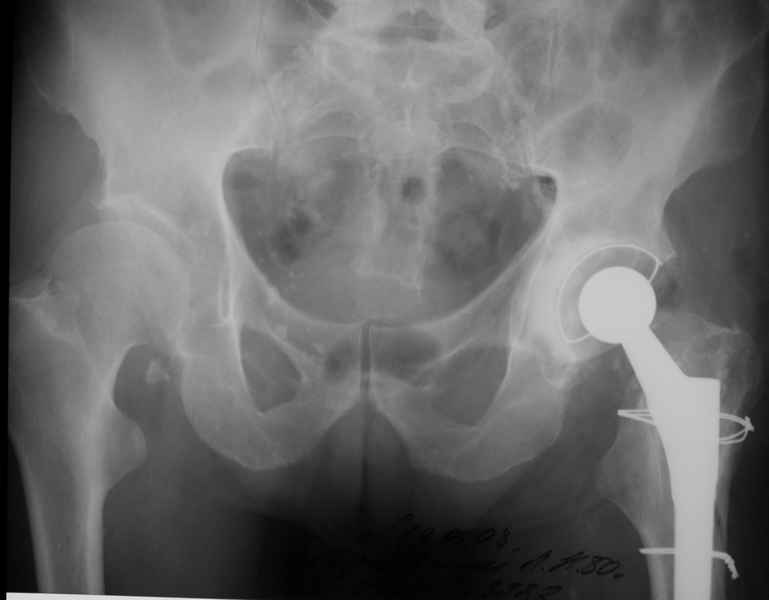

Хочется показать два подобных случая, П-ка З. 72 лет и п-т Г. 80 лет. Сразу принимаю замечание, что это были ножки цементной фиксации, просто под руками не было бесцементника.

Пациента удалось осмотреть недавно. Достигнутый результат сохраняется. Перелом бедра сросся. Конечность опорная и безболезненная, ходит без трости. Ножка, похоже, реинтегрировалась, как и надеялись. Снимки и фото в приложении. Комментарии приветствуются.

Надо ли что-то делать дальше, как полагаете? Убрать винты? Убрать "удлинитель ножки"? Или оставить все, как есть? Спасибо заранее.